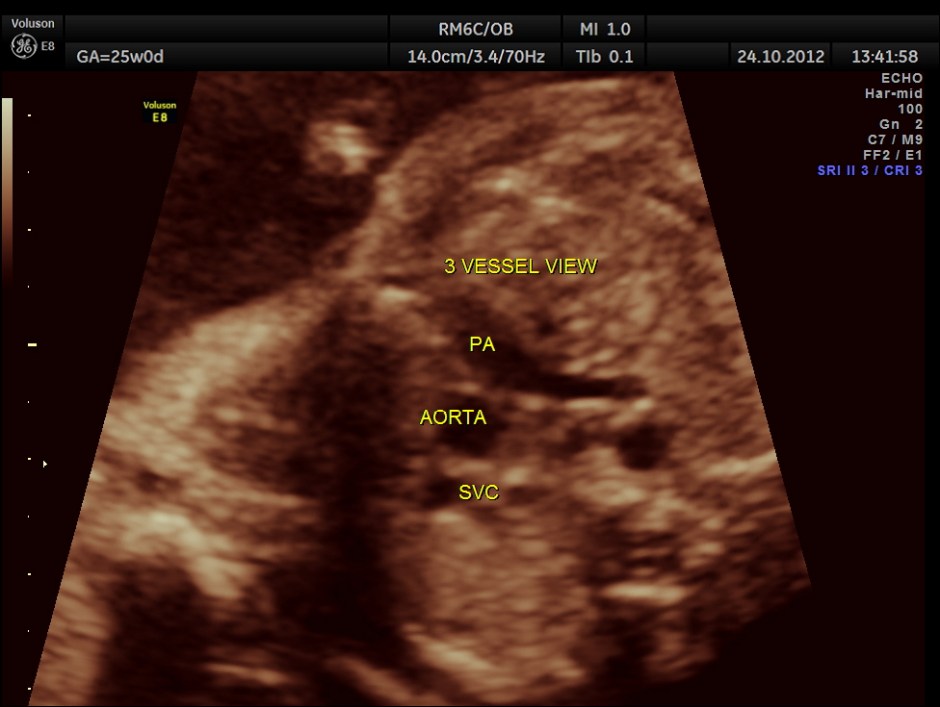

The scan was done around 25 weeks of gestation :

colour flow clearly demonstrating the atrio ventricular septal defect

Spectral doppler shows high velocity flow across the defect